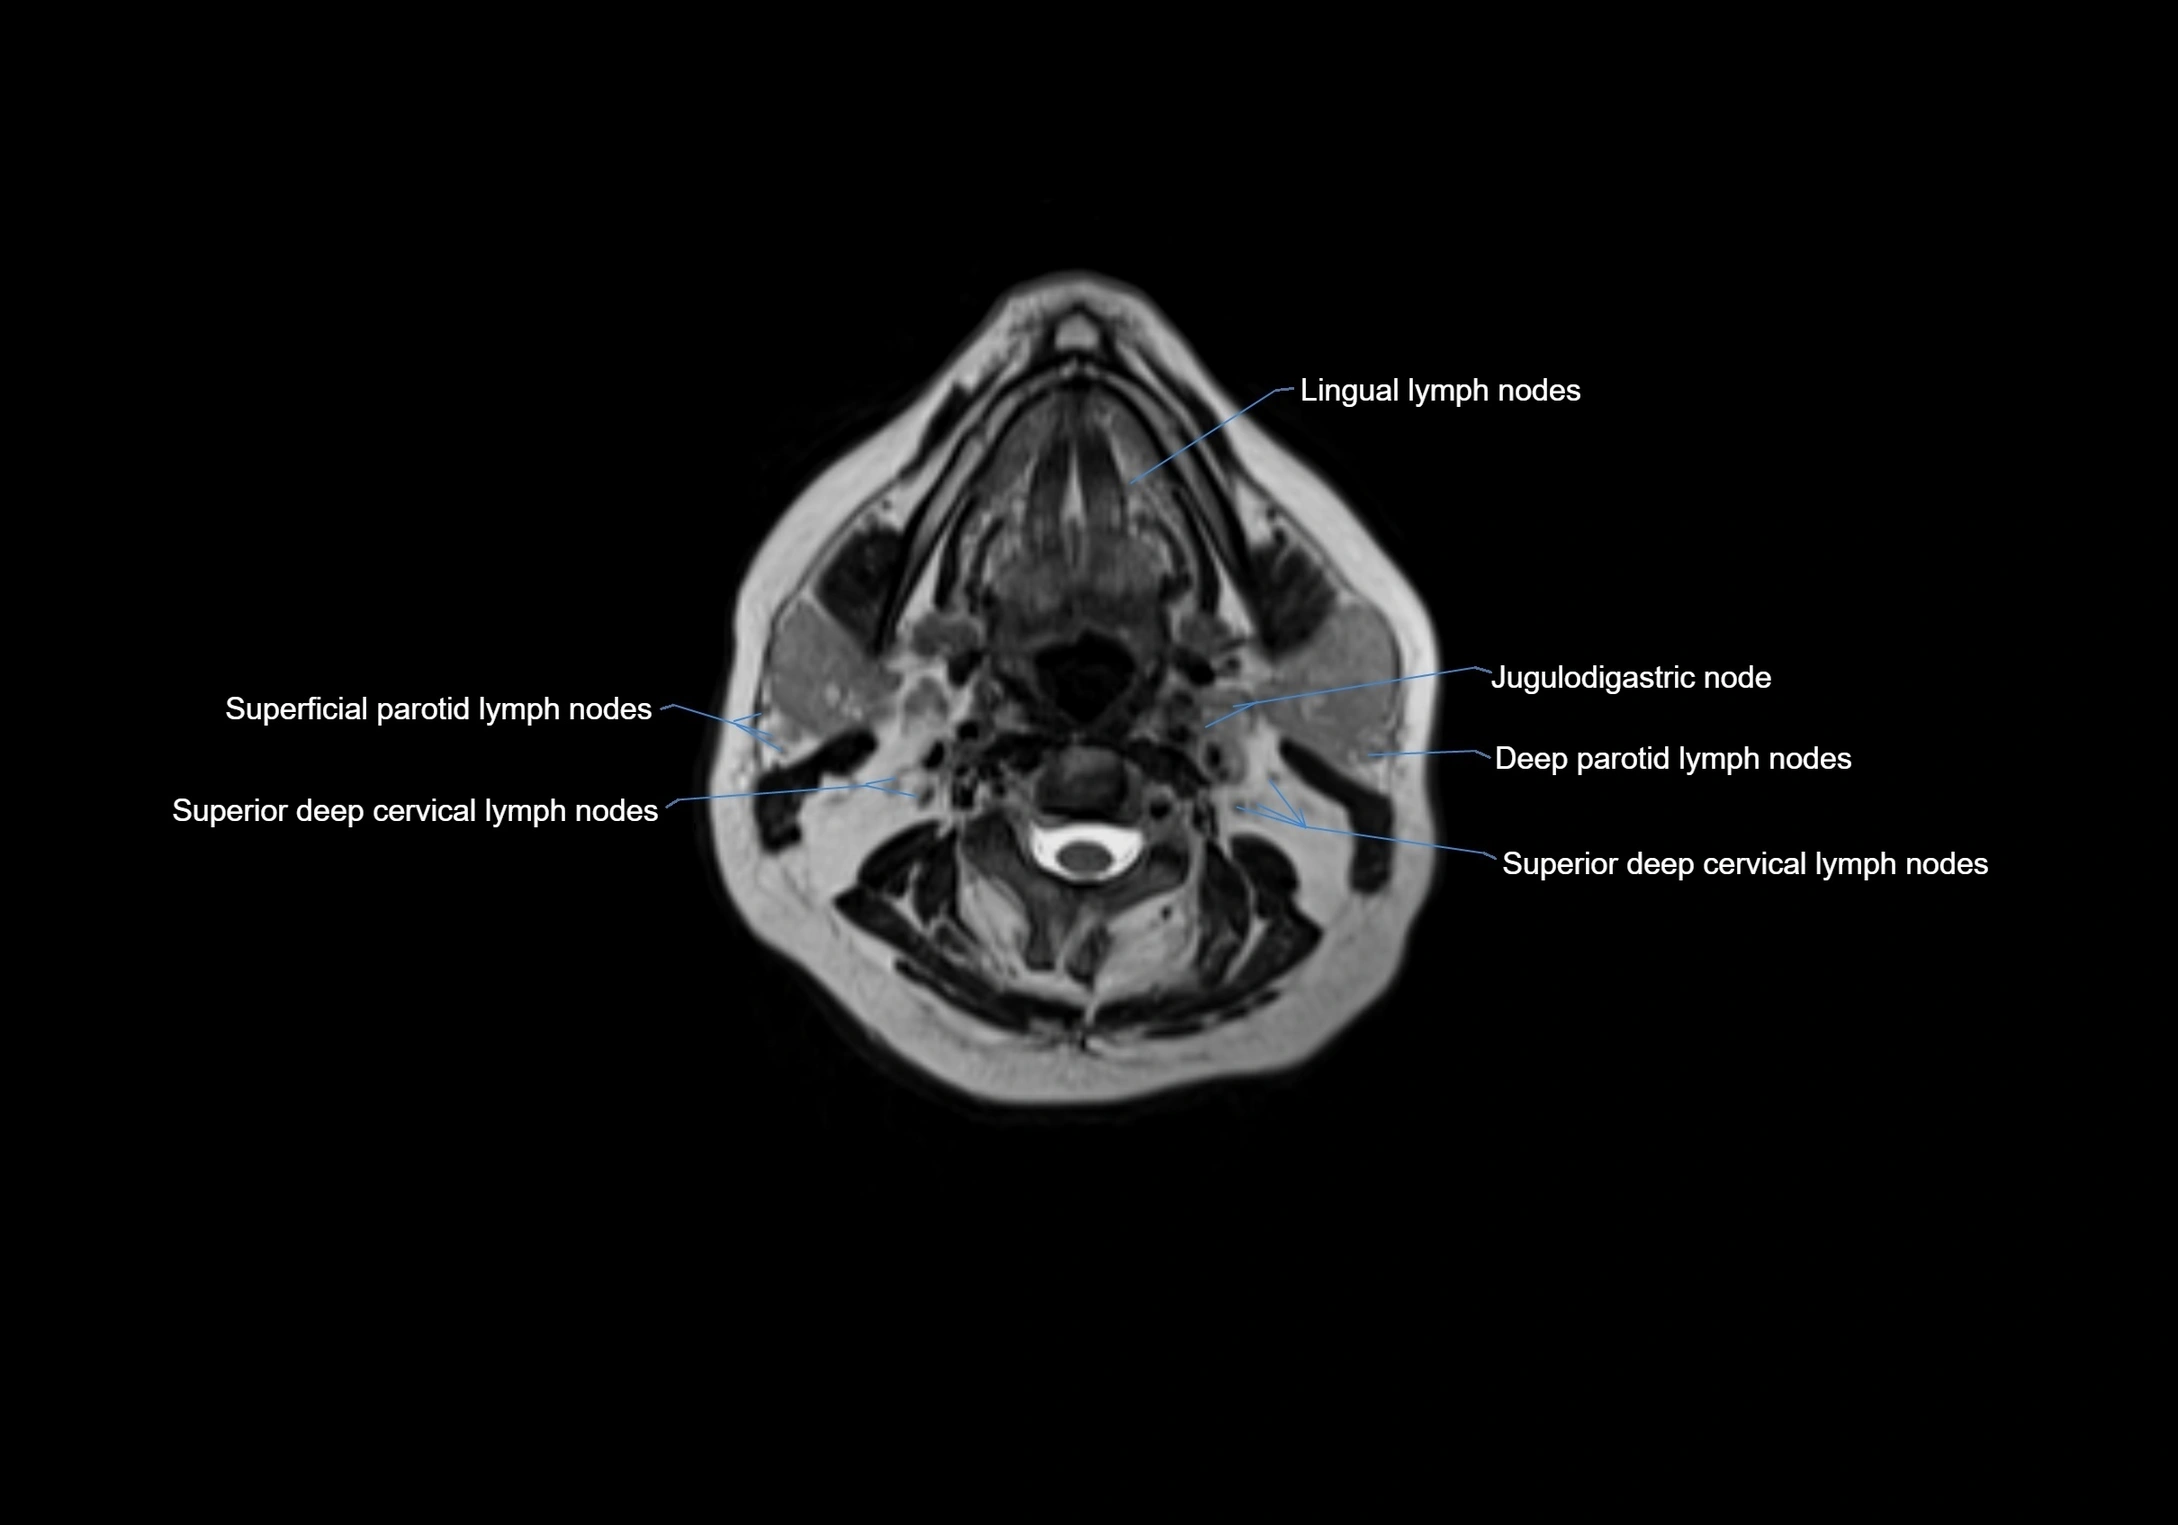

Accessory lymph nodes

Accessory lymph nodes are small, secondary lymph nodes located along the main facial and cervical lymphatic chains, often adjacent to primary lymph nodes, such as preauricular, submandibular, or occipital nodes. They are typically less than 5 mm in diameter, embedded within subcutaneous fat or connective tissue, and may be variable in number and location. These nodes provide additional filtration and immune surveillance for lymph collected from the face, scalp, and neck regions. Accessory lymph nodes are usually non-palpable in healthy individuals but may enlarge in response to infection, inflammation, or metastasis, making them clinically significant.

Location

• Found along primary lymph node chains, including preauricular, submandibular, parotid, and occipital regions

• Embedded in subcutaneous fat or superficial fascia, often lateral or posterior to primary nodes

MRI images

image